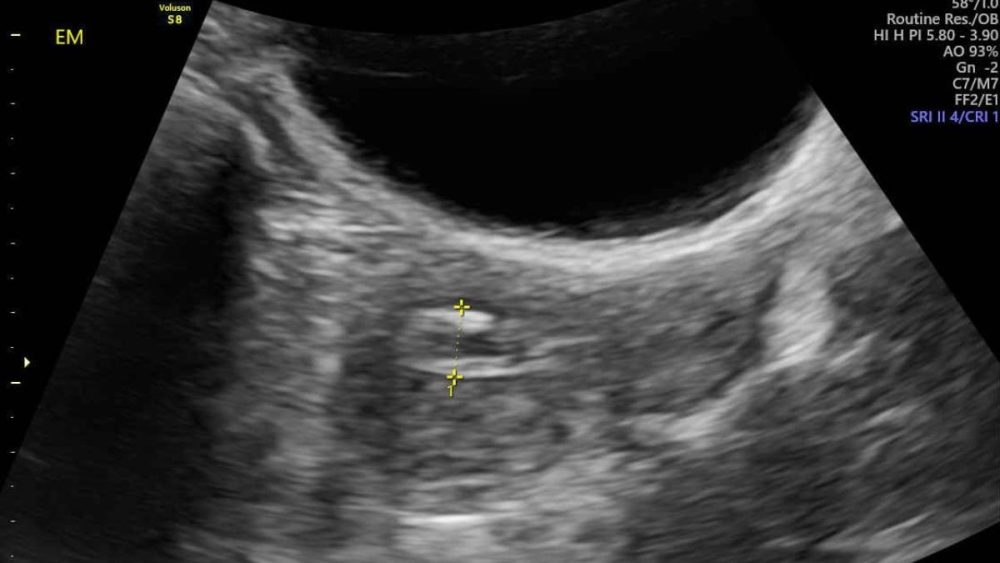

这起病例发生在李女日前不明原因出现持续性阴道出血,虽然家人一开始轻忽,还开玩笑说她像“年轻回来”,但她的侄女身为护理人员,警觉这可能非同小可,立即要求她到诊所检查。初步超音波显示子宫内膜增厚,服药后出血仍未改善,转诊至台中荣总妇女医学部进一步检查后,切片证实为子宫内膜癌。